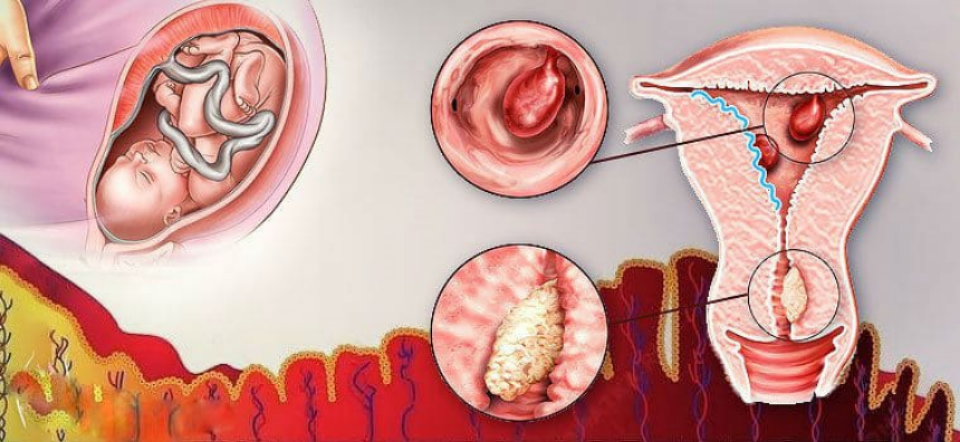

Анатомия женского организма: строение и функции матки